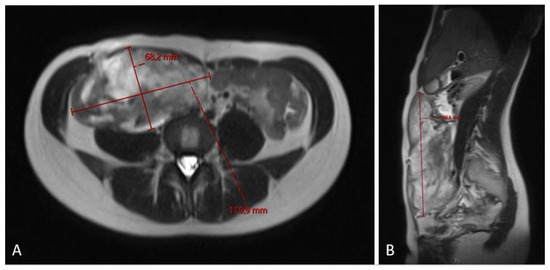

Figure 5.

MRI scan ((A)—axial plane; (B)—sagittal plane) after 3 cycles of chemotherapy showing no effect of the treatment and slight progression in the craniocaudal tumor size (12.0 × 6.6 × 20.0 cm).

The 3-month MRI control showed a stable tumor size; however, the MRI check at the 6-month follow-up showed significant tumor growth progression (Figure 4), sized 10.5 × 6.2 × 17.5 cm in craniocaudal diameter located in the musculus rectus abdominis on the right side. She was recommended to stop oral contraceptives and preventive devices (IUD) containing estrogen and/or progesterone and was referred to the National Oncology Center for further treatment, where the tumor board determined to administer chemotherapy, and the treatment started with three cycles of Caelyx (doxorubicin hydrochloride), 40 mg/m2 every fourth week, with MRI control afterwards. The patient suffered side effects in form of skin rashes, allergic respiratory problems, and mucositis. She received 60 mg of Caelyx by IV each cycle. The control MRI scan showed no effect of treatment; furthermore, there was a slight progression in the craniocaudal tumor size (12.0 × 6.6 × 20.0 cm), (Figure 5). As the oncologist awaited the latest response to chemotherapy, the further plan was to continue the same treatment options (Caelyx, although at a reduced dose, set to 30 mg/m2) due to the previous side effects. The patient underwent three further cycles with total dose of 47 mg doxorubicin at each cycle. The MRI scan after six cycles showed partial regression of the tumor, now sized 11.2 × 5.4 × 19.1 cm. She was continuously monitored by the surgeon and radiologist with MR scans every 4 months, and the 12-month scan after chemotherapy showed significant tumor regress, sized only 1.2 × 3.7 × 8.7 cm (Figure 6). Five weeks later, the patient became pregnant and was referred from the midwife for gynecological control, starting on week 12 + 4.